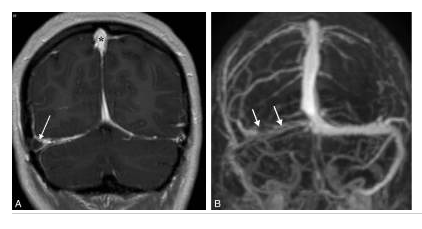

Thrombose du sinus latéral droit en IRM.

Coupe frontale pondérée en T1 avec injection (A) : opacification normale des sinus sagittal supérieur et latéral gauche (astérisques), défaut d’opacification du sinus latéral droit thrombosé (flèche), réalisant un signe du delta. L’ARM veineuse (B) retrouve le défaut d’opacification du sinus latéral droit (flèches).